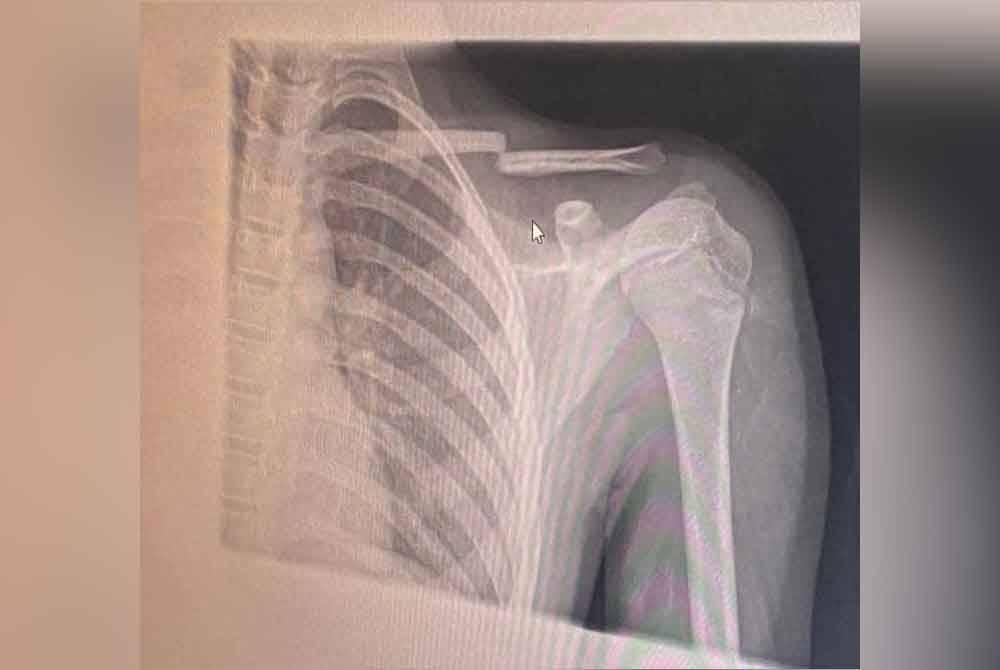

KAJANG – A 12-year-old boy suffered a broken collarbone after being pushed to the ground in what his mother described as the most serious bullying incident he has endured at a religious primary school here.

"This incident, which caused his collarbone to break, is too serious. I lodged a police report, and the investigating officer came to the school, took statements from the headmaster, class teacher, several witnesses and parents,” she told Sinar.